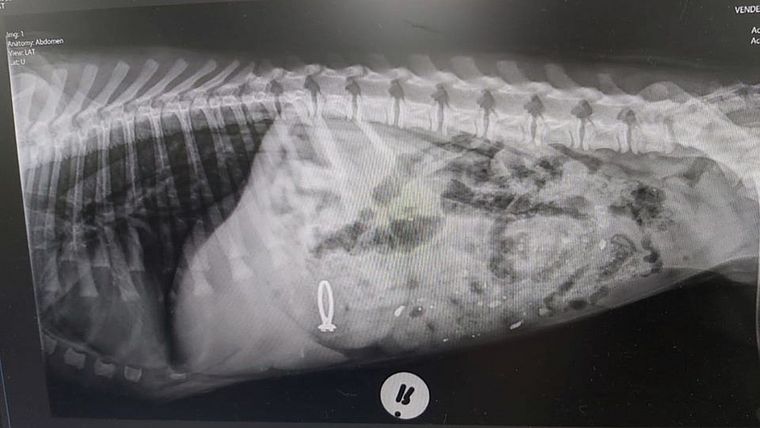

“Meu nome é Pepper. Pareço um pouco enjoada? Isso é porque o veterinário deu algo para me fazer vomitar! Não porque ele é mau, mas porque eu comi o anel de noivado da minha mãe!!!” disse o hospital onde Pepper foi levado na África do Sul. Após perceber que seu anel tinha ido parar no estômago de Pepper, a moça foi diretamente ao hospital The Valley Farm Animal Hospital.

Foi realizado o procedimento de raio X e logo o anel ficou visível na barriga do cão. O veterinário induziu Pepper ao vômito, e conseguiu tirar o objeto, que voltou novinho em folha à sua dona. Alguns comentários diversos sobre a situação foram gerados na rede social, “Desculpe mas eu não conseguiria fazer um cãozinho ficar enjoado. Preferiria esperar as consequências”, um dos internautas comentou, discordando da atitude do veterinário.